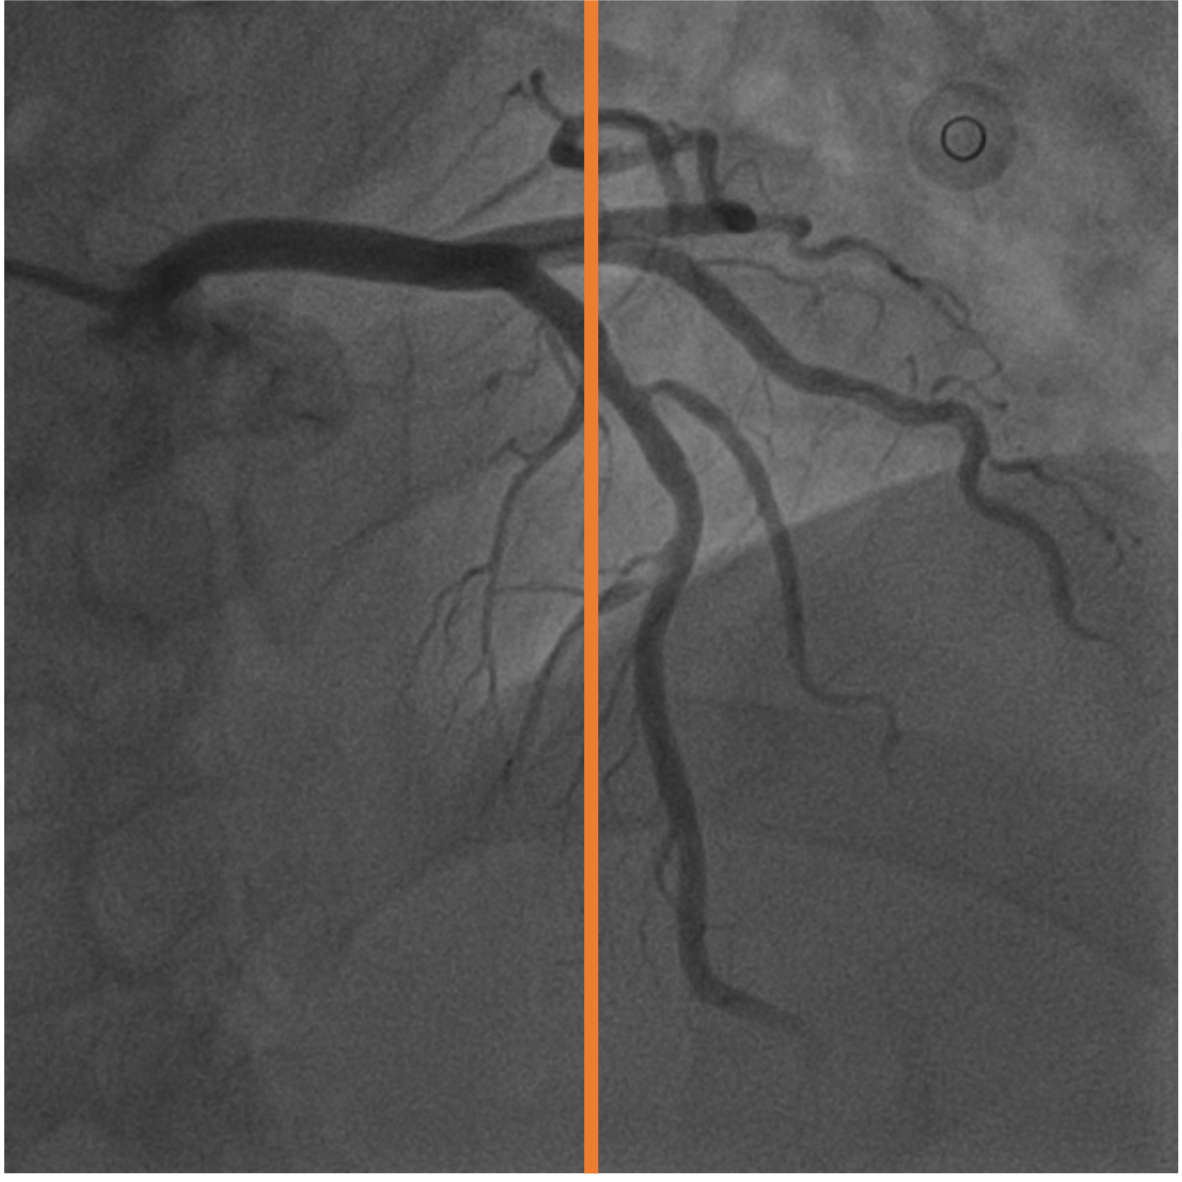

4.1 XACV Dataset

We collect 111 complete records of coronary artery X-ray videos from 59 patients, encompassing the injection, flow through the blood vessels around the heart, and dissipation of the contrast agent. Subsequently, we establish the XACV (X-ray Angiography Coronary Video) dataset. Each video consists of an average of 86 frames of high-resolution coronary artery X-ray images, with an equal distribution of left and right coronary arteries. We invite experienced radiologists to annotate the vascular regions, focusing on one or two frames where the contrast agent is most prominent in each video. These annotations are used only for evaluation in our method, not for training, maintaining the unsupervised nature of our approach. The data collection protocol involves several key steps, including patient preparation with informed consent and metal object removal, image capture using a Philips Allura Xper FD20 machine for standardized frontal (PA) and lateral views, DICOM file storage, and de-identification for patient privacy. Experienced radiologists perform diagnostic annotations using standardized tools and methods, with multiple annotations to enhance accuracy. Quality control measures, secure data management, and strict adherence to ethical guidelines and privacy regulations are implemented throughout the process. The XCAD dataset contains only a single image, and the CADICA video dataset does not provide corresponding ground truth. Therefore, in the following experiments, we conduct all the analyses on our collected XACV dataset and the corresponding GT for each sequence. In Figure 5, we show that compared to other publicly available datasets, XCAD (Ma et al., 2021) and CADICA (Jiménez-Partinen et al., 2024), our dataset exhibits finer annotations in the vascular regions, providing an advantage for future related tasks. The development and use of our dataset have been approved by our institution’s IRB. We will make the XACV dataset publicly available.

Since supervised training and testing data are from the same dataset (in-domain setting), its performance will be better than that of self-supervised or unsupervised methods. However, it is worth noting that in this scenario, our method does not require any labels and can still outperform existing self-supervised methods. Also, we test the CADICA dataset to compare the generalization ability of supervised training and our proposed unsupervised training in Figure 8. We find that supervised methods are limited by the domain of their training data and thus struggle to generalize well. Our method, while requiring test-time training, can adapt to various datasets in an unsupervised manner. This allows for greater flexibility and generalization across different types of vascular video data.

We calculate the AUROC and AUPRC in Figure 6. We normalize the model’s final layer output to [0, 1] to use it as the probability for calculating AUROC and AUPRC. Our model performs favorably against other methods on both AUROC and AUPRC. We also provide visual comparison results in Figure 7, demonstrating our vessel segmentation results are more accurate, complete, and closer to the ground truth masks. Moreover, in some sequences, our method even performs on par with supervised U-Net (Ronneberger et al., 2015), as U-Net might face an overfitting problem with insufficient training data. Additionally, we provide visual comparisons on the CADICA (Jiménez-Partinen et al., 2024) dataset, which is also a coronary artery X-ray video dataset but without ground truth labeling. Figure 8 demonstrates that our test-time training scheme generalizes better than existing methods. Due to the space limit, we provide more visual comparisons in the appendix.